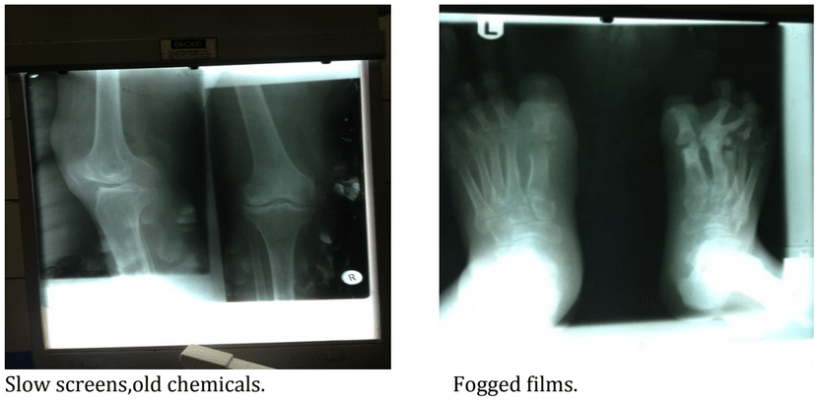

All diagnostic images now have a radiopaque marker and all extremities are imaged with both an AP and Lateral view. Using past images and those taken during my first week, we were able to create updated exposure charts for both adults and children. These are now not only stored in Moses’ head but in his office for future radiographers. Some of our early films were diagnostically poor quality due to the processing chemicals natural oxidation and age. The greater the agitation in the water tank, the dirtier the films were getting so our solution was to wash the excess fixer off films under the one running water tap. The darkroom is based adjacent to the x-ray room and with no ventilation it doesn’t take long for the fumes to accumulate and leaving your taste buds struggling to comprehend.